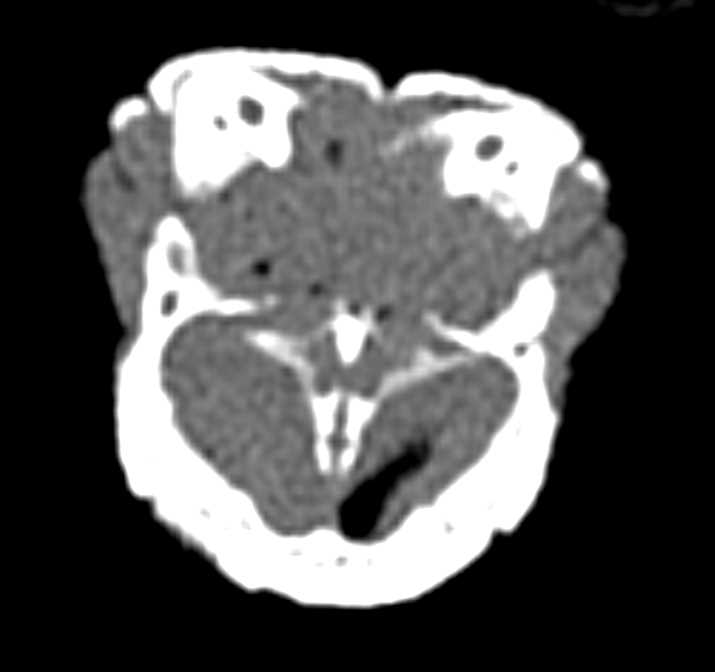

Blue Tongue Skink